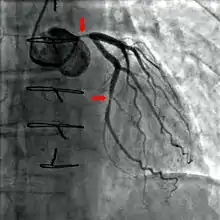

Coronary catheterization is one of the several cardiology diagnostic tests and procedures. Specifically, through the injection of a liquid radiocontrast agent and illumination with X-rays,[1] angiocardiography allows the recognition of occlusion, stenosis, restenosis, thrombosis or aneurysmal enlargement of the coronary artery lumens; heart chamber size; heart muscle contraction performance; and some aspects of heart valve function. Important internal heart and lung blood pressures, not measurable from outside the body, can be accurately measured during the test. The relevant problems that the test deals with most commonly occur as a result of advanced atherosclerosis – atheroma activity within the wall of the coronary arteries. Less frequently, valvular, heart muscle, or arrhythmia issues are the primary focus of the test.

If atheroma, or clots, are protruding into the lumen, producing narrowing, the narrowing may be seen instead as increased haziness within the X-ray shadow images of the blood/dye column within that portion of the artery; this is as compared to adjacent, presumed healthier, less stenotic areas.